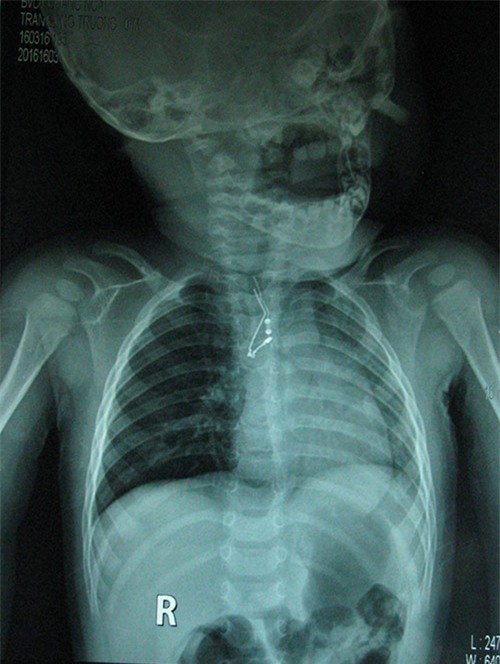

22 giờ cùng ngày, cháu được chuyển lên bệnh viện Đa khoa Đà Nẵng. Qua phim chụp X-quang, bác sĩ xác định trong phế quản của cháu có một dị vật. Sáng hôm sau, cháu được gây mê, nội soi phế quản, lấy dị vật là tụ điện tử ra.